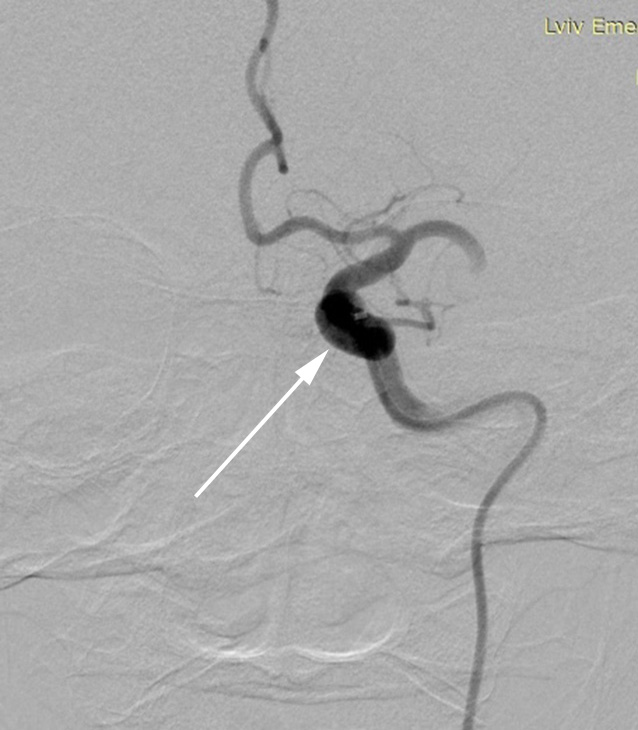

In all cases, direct intraoperative AP measurements were performed in the С1-segment of the internal carotid artery (ICA) proximal to the site of occlusion, both before and after thrombectomy (ICA-pre and ICA-post, respectively), and in the М1-segment of the MCA at the occlusion site prior to MT (MCA-pre) (Fig. 1).

A B C

Fig. 1. Catheter positioning during invasive AP measurement: A – in the internal carotid artery (ICA) before thrombectomy (via aspiration catheter); B – in the middle cerebral artery (MCA) distal to the thrombus (via microcatheter); C – in the ICA after thrombectomy. Arrows indicate the location of the distal catheter markers